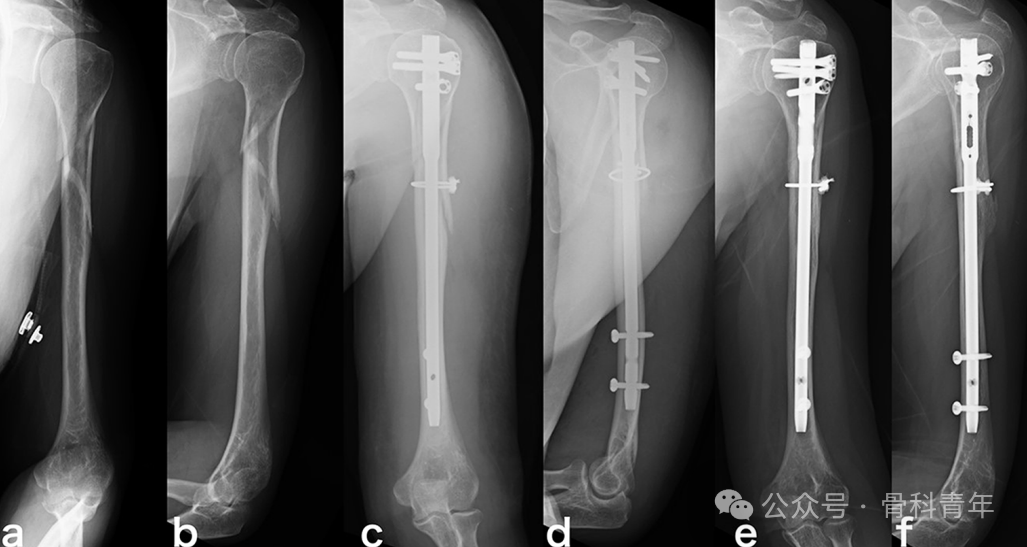

肱骨干“蝶形骨块”多见,文献介绍了合并蝶形骨块的肱骨干骨折(a,b),行髓内钉固定后,蝶形骨块未固定(c,d),术后12月出现骨折不愈合(e,f),后经植骨翻修(g,h)。

而一期行钢丝环扎组,则获得了预期的骨愈合。

文章结果表明,对合并蝶形骨块的肱骨干骨折,尽管钢丝环扎或增加手术时间和增加术中出血,但能避免骨不连。提示钢丝环扎有益。